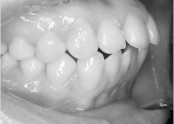

• 치아교정 덧니 교정

• 36